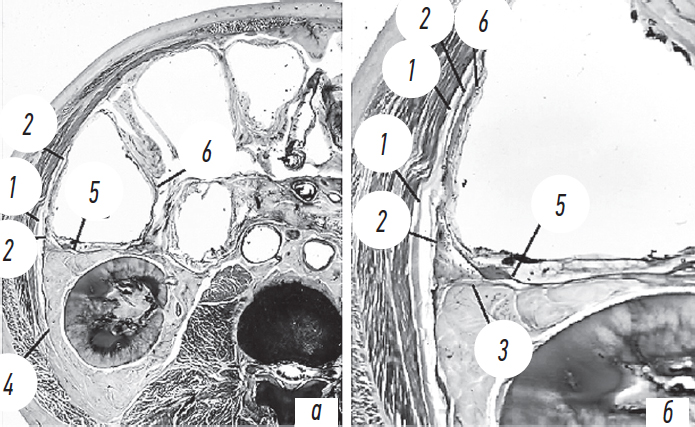

В дальнейшем в ходе препаровки установлено, что забрюшинная фасция образована соединением двух листков фасции Герота, а по направлению кпереди она располагается в слое между поперечной фасцией и брюшиной, т. е. ее непосредственным продолжением в передних отделах брюшной стенки является предбрюшинная фасция. Данное предположение подтверждено в ходе прицельного изучения особенностей топографической анатомии на прозрачных пластинированных срезах человеческого тела (рис. 5).

Рис. 5. Фасциальные структуры забрюшинного пространства: a — общий вид поперечного распила брюшной стенки; б — прицельное увеличение. 1 — поперечная фасция; 2 — забрюшинная фасция; 3 — предпочечная фасция; 4 — позадипочечная фасция; 5 — позадиободочная фасция; 6 — брюшина

Исследованы ход листков фасции Герота и их взаимоотношение со слоями передней брюшной стенки. Установлено, что забрюшинная фасция начинается не от брюшины, а тесно прилежит к ней и является при этом самостоятельным фасциальным листком, направляющимся к передней брюшной стенке. На препаратах, выполненных путем сложной технологии пластинации среза эпоксидной смолой, некоторые «тонкие» анатомические структуры не могут быть визуализированы. При изучении данных гистотопограмм не удалось достоверно проследить продолжение забрюшинной фасции в предбрюшинную фасцию и далее в фасциально-апоневротический аппарат передней брюшной стенки.